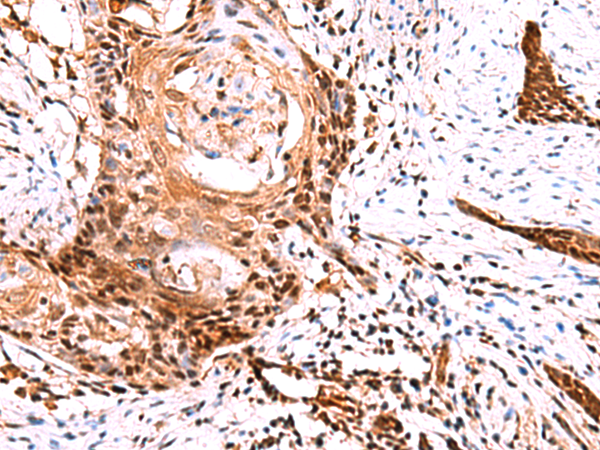

IHC positive control: |

Human esophagus cancer |

IHC Recommend dilution: |

50-300 |